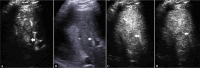

Intrahepatic cholangiocarcinoma (ICC) is a rare, heterogeneous, highly lethal tumor of the biliary tract. Due to the lack of effective treatments, an early identification of ICC is essential to achieve the best outcome in terms of therapy and prognosis aiming for a curative intent. ICC may arise on a normal liver or with an underlying liver disease, making the diagnosis more difficult and complex. Contrast-enhancement ultrasound (CEUS) is an accurate procedure able to detect ICC-specific contrast vascular pattern, and thus facilitating the correlation between radiological and histopathological findings with high specificity and sensitivity. CEUS has been shown to have a high diagnostic potential in the diagnosis of ICC thanks to the possibility of studying in real time the intralesional microcirculation and evaluating the precocity of the enhancement of the lesion during the arterial phase. All these features allow to differentiate the ICC from hepatocarcinoma (HCC) with high sensitivity and specificity. Furthermore, CEUS is a rapid, non-invasive, non-nephrotoxic or non-allergenic tool. The only limitations CEUS may have are related to the disease site and patient characteristics (obesity) and compliance, including the operator's experience. A clinical evaluation of the patient, together with tumor markers and biochemical tests assessment, to differentiate ICC from HCC are highly suggested.